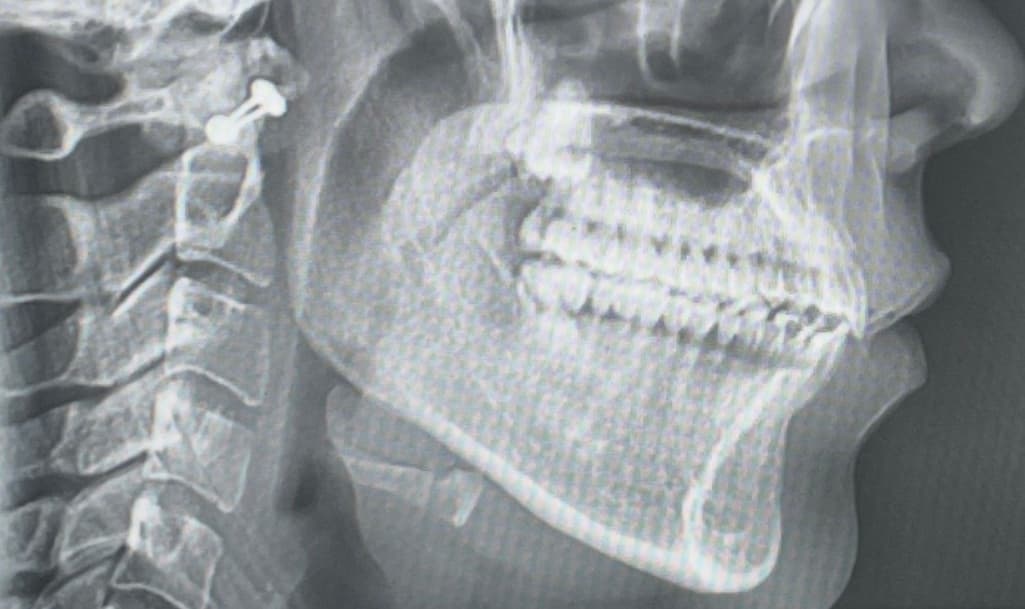

제가 19~21년 치아교정하고 정말 예쁜 교합으로 잘 지내다가 올해 3월 초에 질긴 음식을 먹고 3월 중순 쯤 자고 일어났더니 오른쪽 턱관절이 뒤로 밀려서 (회전해서),개방교합이 생겼습니다. 디스크 쪽 불편함도 있어서 구강내과 치료도 받다가 호전이 없어 구강악안면외과에 갔더니 제가 턱 사이즈가 작은데 , 턱이 뒤에 있어야 편한 위치인데 치아교정은 앞에서 물리게 해놔서 질긴 음식 먹은 충격으로 인해 뒤로 밀린거라 하셔서 하악 수술을 하라고 했는데 아무리 생각해도 너무 의아해서요. 턱 사이즈가 작다고 어느날 이렇게 뒤로 밀리는 일이 생기나요? 저는 아무리 봐도 디스크가 어긋나서 막고있는 것 같아요 CR CO Discrepancy를 언급하시던데 저는 치아교정한 교합으로 정말 편하게 지냈거든요

사진은 순서대로 턱 뒤로 회전하기 전,후입니다.

• 1번 째 사진

3. 현재 엑스레이 사진상으론 어금니 교합은 정상적입니다. 치아 교합보다는 턱관절 문제에 집중해봐야 할 것 같습니다